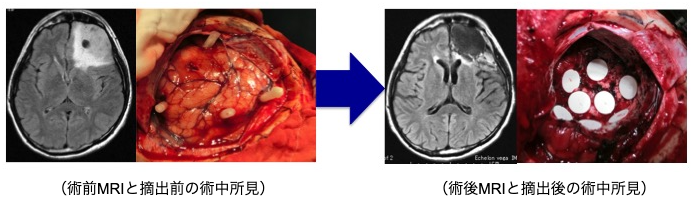

如何に腫瘍を残さず摘出するかが治療成績を左右する疾患であります。このため本腫瘍に対する摘出術において術中MRIを併用することが有用であることはすでに報告されています。当科では術中MRI手術室を有しています。術中MRI手術室を保有している施設は近年増えておりますが、当院は全国で7番目に(2007年12月から)運用を開始しておりました。現在は諸事情により休止中です。